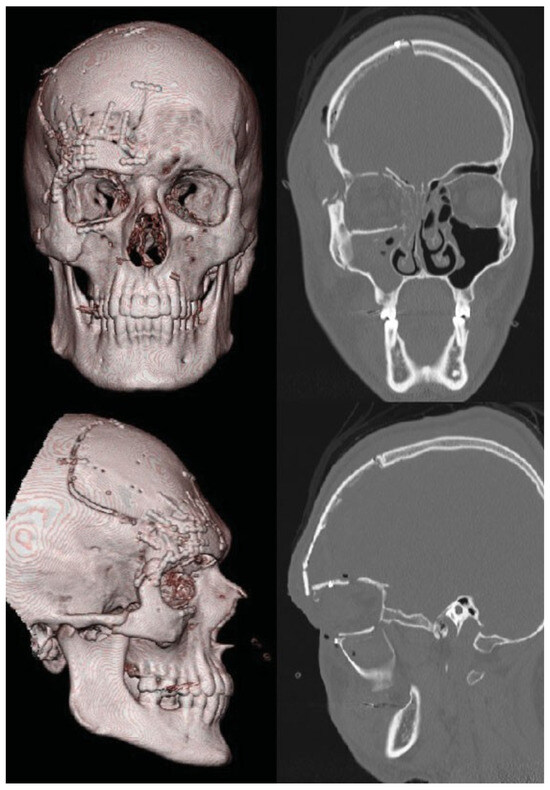

A 27-year old man who presented at the emergency room after a rocket exploded on his right eye on January 1, 2012. The patient was hemodynamically stable on presentation. He could not remember the impact and according to bystanders, the patient was unconscious for several minutes. Substantial periorbital swelling and a laceration above the right eye was seen, and the sensibility of the right cheek was diminished. The ophthalmologist was not able to open his right eye and proper examination of vision was not possible at that moment. During further investigation, the CT scan showed an extensive blow-out fracture of the right orbit, with involvement of all orbital walls and the infraorbital canal (Figure 5). The right globe was completely ruptured. The fracture extended cranially into the frontal sinus, with fracturing of the internal and external wall. Multiple bone fragments were displaced intracranially, accompanied by a subarachnoidal hemorrhage and multiple cerebral contusions. Also, a zygomaticomaxillary complex fracture was described. Consultation of oral and maxillofacial surgery, neurosurgery, and ophthalmology was obtained. The patient was brought to the operating room instantly, and an evisceration of the right eye was performed by the ophthalmology team (Figure 6). On hospital day 4, the swelling was significantly less and management of the facial fractures was performed. Via a coronal incision, the right frontal sinus was approached. The neurosurgery service performed a craniotomy and closed several dura leaks. Next, the posterior wall of the frontal sinus was removed and the nasofrontal duct obliterated, thereby achieving cranialization of the right frontal sinus. Bone fragments of posterior wall were used for reconstruction of the anterior frontal sinus wall and the defects in the orbital walls (Figure 7). The zygoma fracture was reduced and fixated. Recovery was uncomplicated and patient was discharged after several days of observation. A month posttrauma, an acrylic ocular implant was placed by the ophthalmology team. The result was esthetically suboptimal, due to the acquired enophtalmic state of the right orbit. For this reason, reconstructive surgery was performed 18 months posttrauma, in which the right orbital floor was reconstructed using a titanium mesh plate. In the same session, an entropion correction was done by the ophthalmology service (Figure 8). Sensibility of the regions enervated by the second and third trigeminal branch remained disturbed due to damage of these nerves.

Figure 7. Postoperative three-dimensional reconstruction image (left) and computed tomography scan (right) of patient 1 after reconstructive surgery, coronal plane (above) and sagittal plane (below).